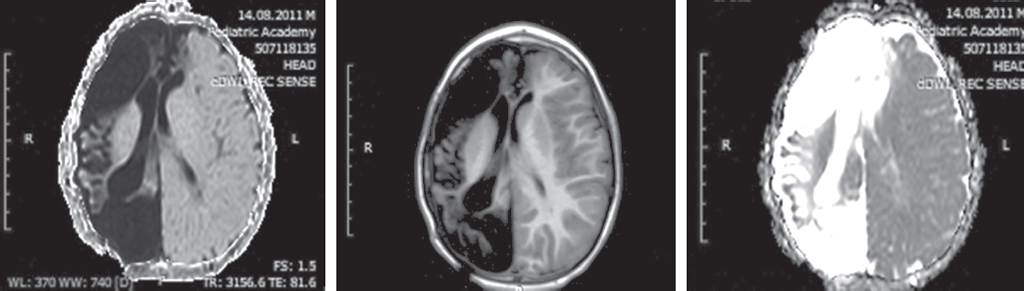

The relevance of studying the consequences of hemorrhagic strokes in young children is due to the frequency of cerebrovascular pathology, the formation of persistent neurological deficits, including post-stroke epilepsy, and high mortality. It is known that hemorrhages are diagnosed in the first 28 days of life in 6-7 out of 100,000 infants, in children from the 28th day of life to 18 years of age from 0.7 to 5.1 cases per 100 thousand children. Mortality in hemorrhagic and ischemic strokes in children ranges from 7 to 28%. Epileptic seizures of the acute and acute period of stroke are prognostically unfavorable factors of the course of the disease. The article presents brief literature data on the etiology and localization of hemorrhagic strokes, their role in the formation of pharmacoresistant epilepsy. Special attention is paid to the role of late hemorrhagic disease of newborns, accompanied by intracranial hemorrhages, in the formation of structural epilepsy in the future. The paper describes own clinical observations of 25 patients suffering from epilepsy after a hemorrhagic stroke with a description of the clinical picture, features of paroxysmal states and their therapy, neuroimaging data, electroencephalographic phenomena. A clinical example is presented in which the clinical, anamnestic, electrophysiological data of a patient with pharmacoresistant epilepsy developed as a result of a hemorrhagic stroke on the background of late hemorrhagic disease of newborns are considered.

Structural epilepsy in children, formed after a hemorrhagic stroke, is accompanied by significant multi-regional damage, pronounced neurological deficit and is characterized by a pharmacoresistant course.